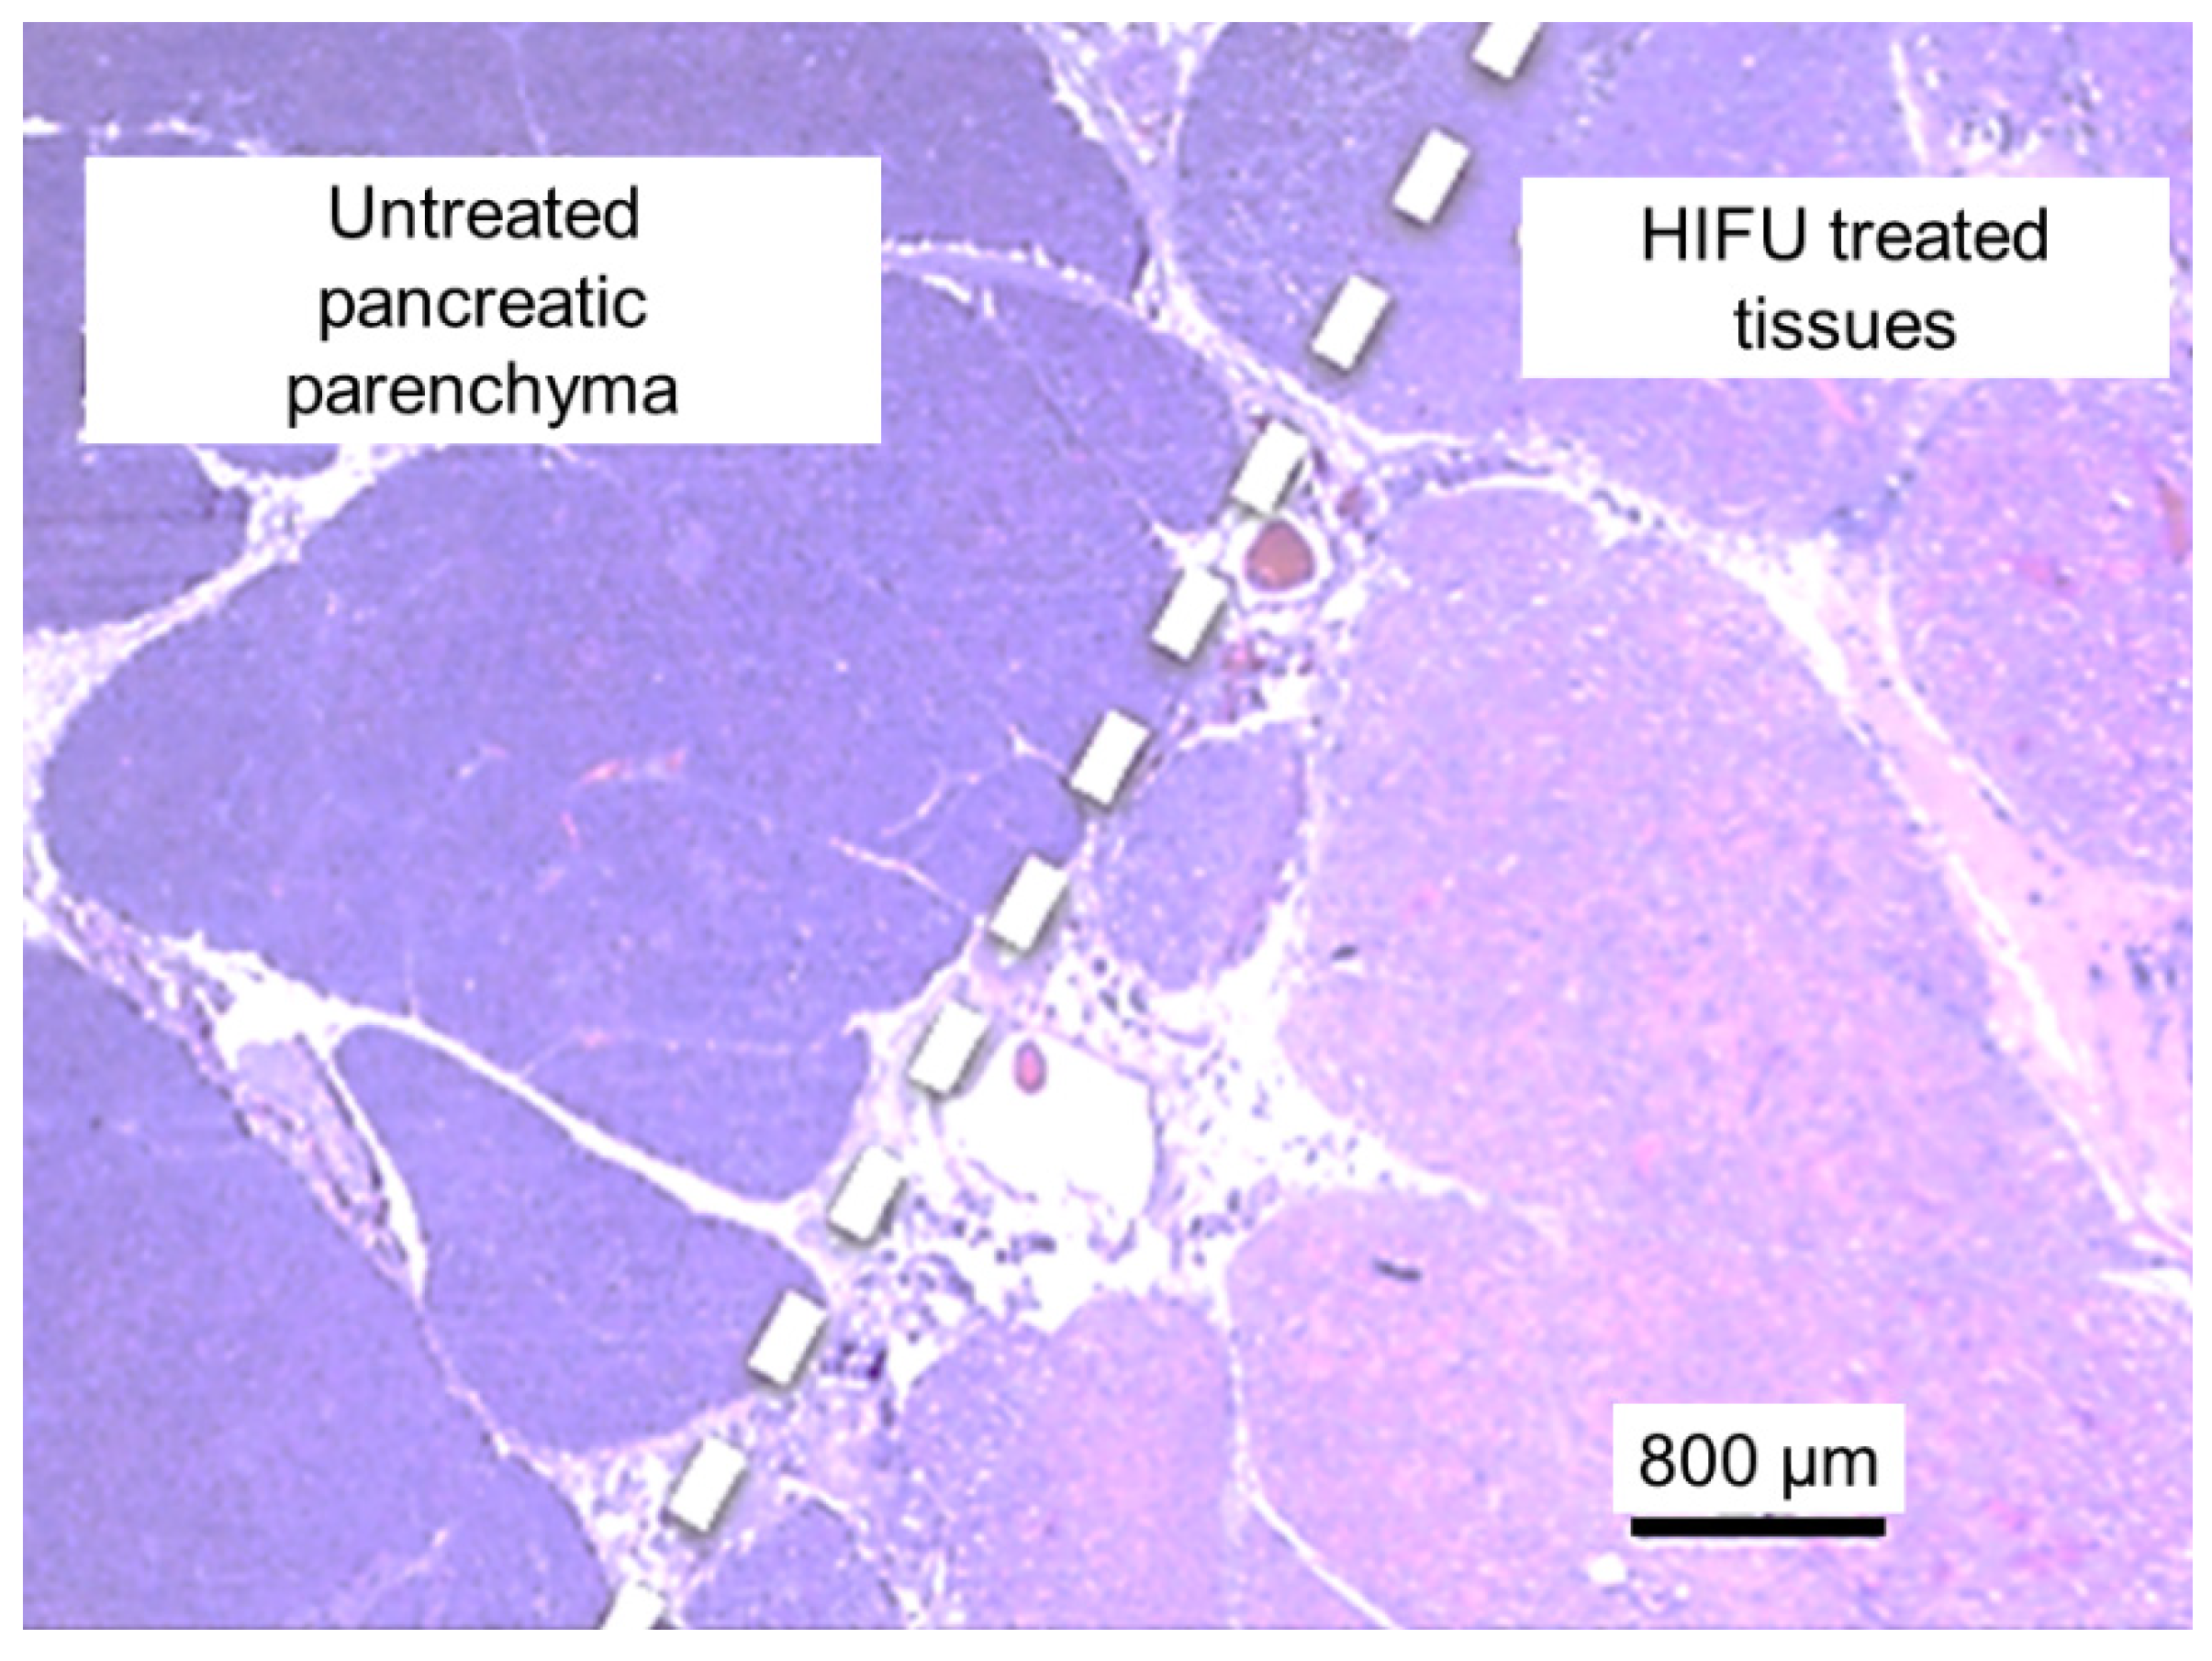

3.3. Analysis of HIFU Treatment